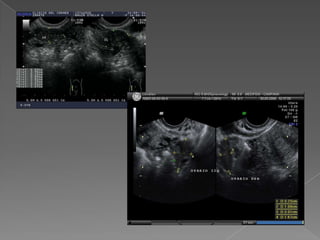

 Visibles acada lado del útero  Reparo: vasos ilíacos  Móviles, posición variable  Estructuras ovoideas , hipoecogénicas, porción central mas ecogénica  Tamaño : 3 cm x 2 cm x 2cm  Volumen : L x AP x T x 0.523  Vol. : 6 a 10 cm cúbicos , max :14 -16  Folículos : fácil identificación  Miden de 2 a 25 mm de diámetro